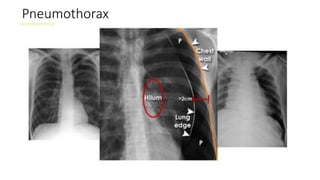

Pneumothorax